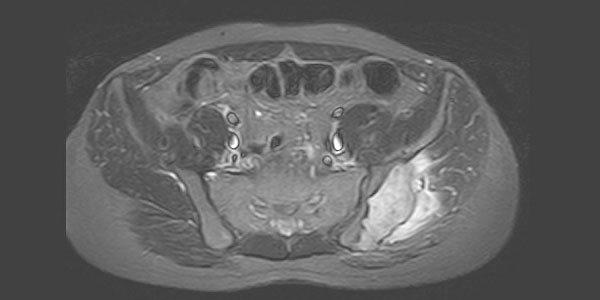

Спинальная метастаза представляет собой распространение рака на кости позвоночника, что часто вызывает боль в спине и другие симптомы. Ранняя диагностика и индивидуально подобранное лечение играют важную роль в улучшении качества жизни и эффективном контроле симптомов.